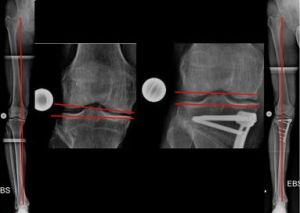

Beidseitige, zuklappende Korrekturosteotomie, kniegelenksnah am Oberschenkel bei X-Bein und fortgeschrittener Arthrose (Bild 9).

Bemerkenswert ist die „Öffnung“ des äußeren Gelenkspaltes, am rechten Bein, durch die Lastumverteilungsmaßnahme. Korrekturen wie diese adressieren nicht nur Knie- sondern auch Beinschmerz.

Sie dienen gleichzeitig der Vereinfachung einer später eventuell notwendigen Versorgung mit einer Gelenkprothese.